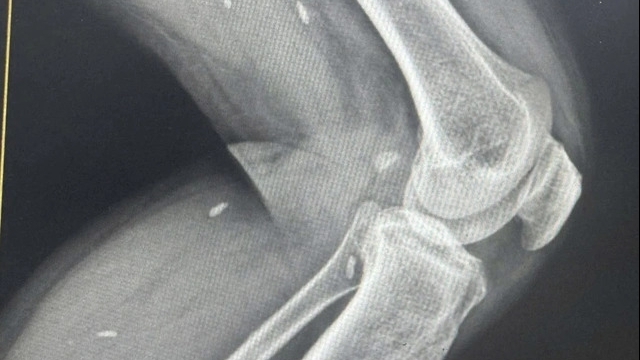

Cháu bé có vết thương bàn tay phải: dập nát đốt 1 ngón III, đốt 3 ngón II, I; vết thương bàn tay trái: dập nát ngón V. Ngoài ra, bệnh nhi còn có vết thương gan bàn tay, đứt gân ngón tay, khuyết hổng phần mềm ô mô cái (thuộc gan bàn tay) và vết thương ở mu chân phải, nham nhở nhiều dị vật.

PGS. TS Nguyễn Mạnh Khánh - Phó Viện trưởng Viện chấn thương chỉnh hình, Trưởng khoa Phẫu thuật Chi trên và Y học thể thao, Bệnh viện Việt Đức cho hay, ngay khi tiếp nhận, các bác sĩ đã tiến hành cắt lọc tổ chức dập nát, sửa mỏm cụt đến các đốt ngón tay cho bệnh nhi, đồng thời cắt lọc phần mềm phức tạp bàn chân phải.